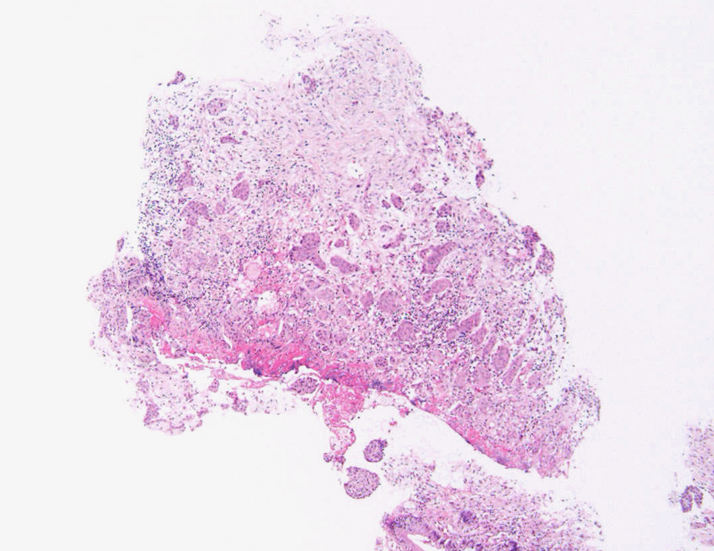

S状結腸粘膜生検組織所見:

粘膜筋板直下に小型胞巣を作って浸潤し炎症性の間質をともなう。 浸潤性増殖のわりに細胞は均一, そんなに異型性も強くない。apoptosisに陥った細胞が散在する。部位によっては胞巣状増殖細胞は細胞間橋がありそうな扁平上皮様に見える。深いところは線維性間質が増えてきて細胞は索状となりcarcinoidなども鑑別候補となるかもしれない。明らかな腺管形成, 粘液産生はみられない。35歳男性, わりとおとなしい扁平上皮癌様の組織か?と生検初見時に考えられた。desmoplasticな間質にもよく観察するとバラけた細胞異型が認められる。 (腫瘍胞巣①, ③)